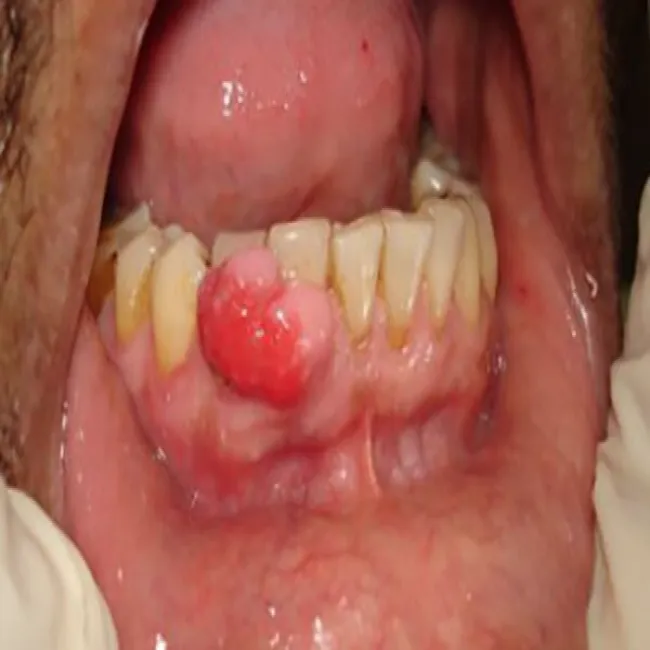

Bąbel na dziąśle nadziąślak

Nadziąślak, epulis

Nadziąślak

Lokalizacja

Jama ustna